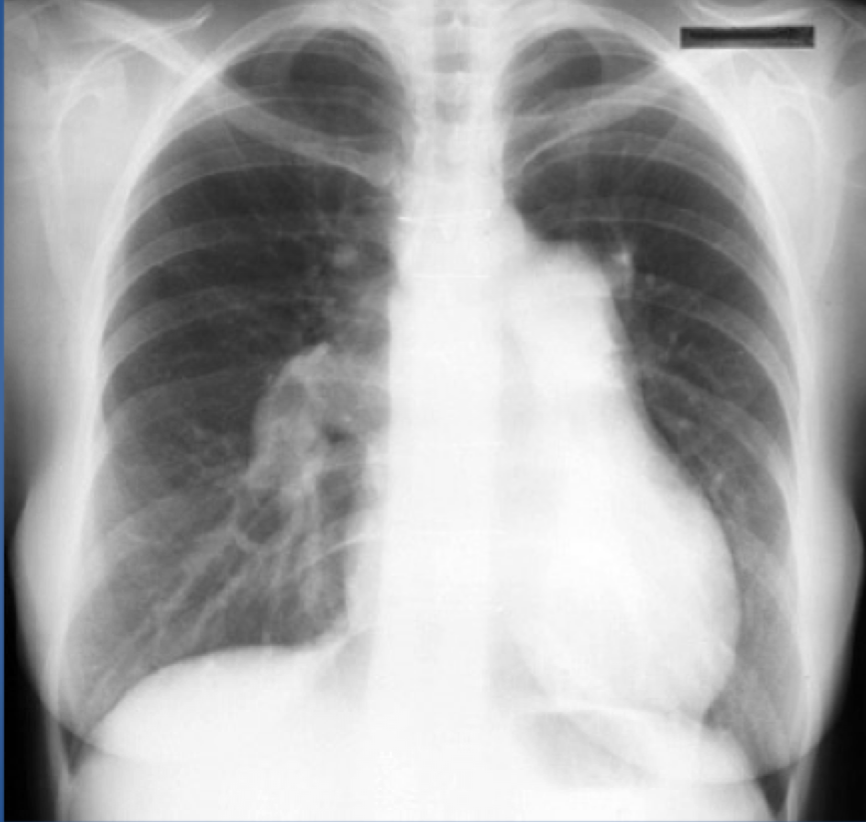

pulmonary HTN!!!! - r heart enlargement and dilated pulmonary arteries

Chronic disease:

- Dilation of right & left main and lobar pulmonary arteries

Advanced disease:

- Right ventricular & right atrial enlargement